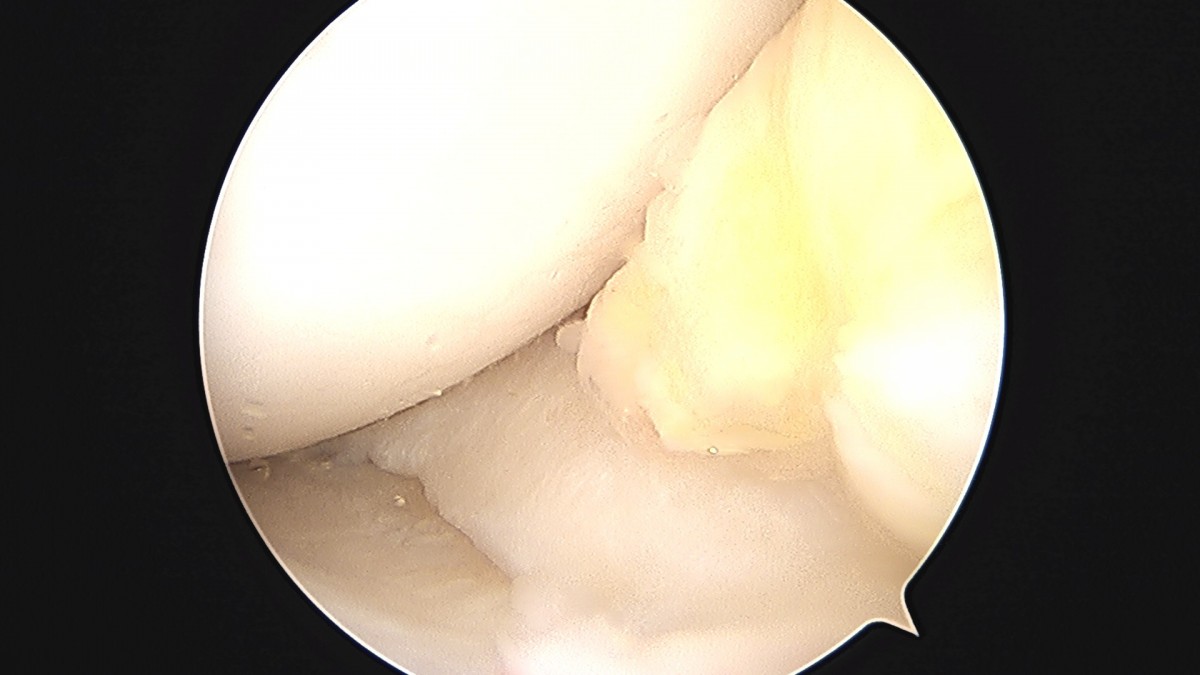

이재상원장님 무릎 반월상 연골판 절제술 강일O 환자

dae765e4d9ac96aee867c9d6292d8784_1758006724_3199.jpg